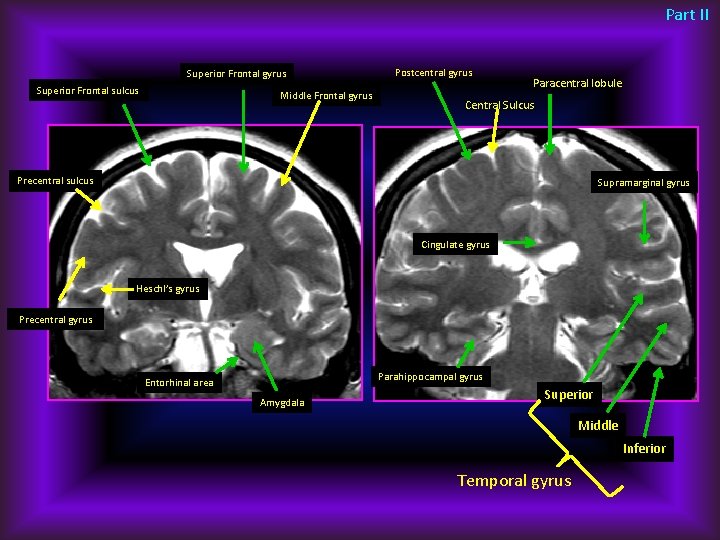

Part II Superior Frontal gyrus Superior Frontal sulcus Middle Frontal gyrus Postcentral gyrus Paracentral lobule Central Sulcus Precentral sulcus Supramarginal gyrus Cingulate gyrus Heschl’s gyrus Precentral gyrus Parahippocampal gyrus Entorhinal area Amygdala Superior Middle Inferior Temporal gyrus